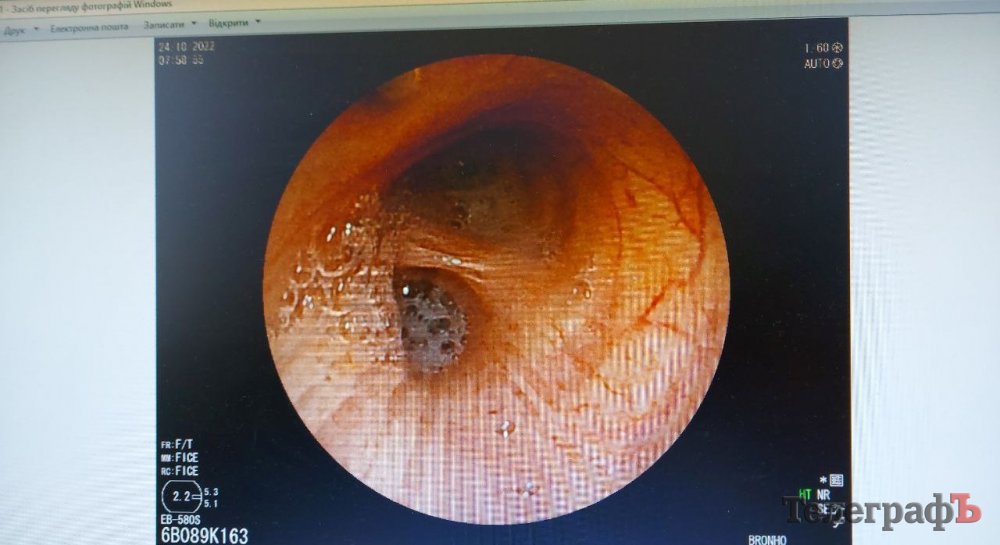

– Тепер маємо гастроскоп експертного рівня, за допомогою нього можна побачити зміни у слизовій оболонці, яких ми раніше не бачили, коли дивилися в окуляр старого гастроскопа. Раніше були апарати, які називалися фіброгастроскопи, вони були низької роздільної здатності, лікарі дивилися в окуляр, де було невелике наближення і могли побачити виразку, ерозію, поліп.

У цього апарату є відеоендоскопічна стійка, процесор, великий монітор високої роздільної здатності. За допомогою гастроскопу, де на кінці чутлива камера, ми можемо бачити такі зміни у слизовій оболонці, що старим гастроскопом просто фізично не могли, бо старі камери не могли передати таку картину. Зараз ми бачимо навіть ворсинки шлунку, кишківника, ворсинчастий епітелій бронхів, – каже лікар.

Новий апарат дозволяє передати фото з обстеження на флешку, щоб потім переглянути його на комп’ютері – це зручно. Також обладнання має різні фільтри, щоб можна було краще розгледіти досліджувану ділянку під різним світлом.

Для порівняння: старий японський апарат